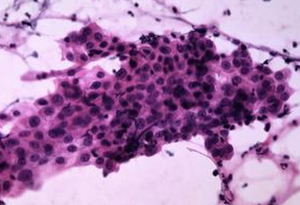

痰脫落細胞(二)液基細胞學(LBC)技術:是一種半自動或全自動標本處理新技術,是將刷取或灌洗法採集的標本,放在特殊的運送液或保存液中,製成細胞懸液,經過進一步處理,除去血液、蛋白和炎性滲出物,製成分布均勻的薄片。本質是濾膜過濾法實現了自動化。其優點是:①塗片上細胞分布均勻、分布範圍小、背景清晰。②標本篩查簡便、快速。③能提高診斷靈敏度和特異度。④能顯著降低標本的不滿意率。⑤能用於原位雜交和免疫細胞化學染色。

許多用於組織切片的染色方法也適用於細胞病理學塗片。不同染色技術均適用於婦科或非婦科標本的永久性染色。巴氏染色法適用於濕固定塗片。蘇木素和伊紅染色法(HE染色法)是組織切片最常用的方法,也是許多細胞病理學實驗室常用的染色方法。其他常用染色方法有組織細胞化學染色,如過碘酸Schiff染色、三色染色、Zie-hl-Neelsen染色、Gram染色和Grocott碘化銀染色和有助於識別微生物或鑑別腫瘤細胞分化程度的免疫細胞化學染色等。 ①巴氏染色特點:是細胞具有多色性的染色效果,色彩多樣且鮮艷。塗片染色透明性好,細胞質顆粒分明,細胞核結構清晰。如鱗狀上皮完全形化細胞胞質呈桔黃色;不完全形化細胞胞質呈粉紅色;而角化前細胞胞質呈淺藍色或淺綠色。適用上皮細胞染色或陰道塗片中觀察女性激素水平對上皮細胞的影響。此方法的缺點是染色程式較複雜。 ②蘇木素-伊紅染色法(hemotoxylin-eosin,H-E)染色特點:透明度好,細胞核與細胞質對比鮮明,染色效果穩定。細胞質染成淡玖瑰紅色,細胞核染成紫藍色。紅細胞染成朱紅色。染色步驟簡便,適用於痰液塗片。③瑞氏-吉姆薩染色法(Wright-Giemsastaining)特點:細胞核染色質結構和細胞質內顆粒顯示較清晰。此方法多用於胸腹水、前列腺、針吸細胞學及血液、骨髓細胞學檢查。操作簡便。